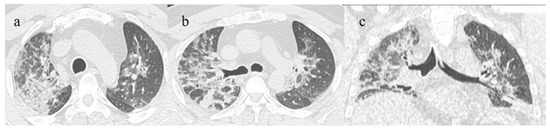

3.3.1. Acute Respiratory Distress Syndrome

3.3.2. Pneumomediastinum and Pneumothorax